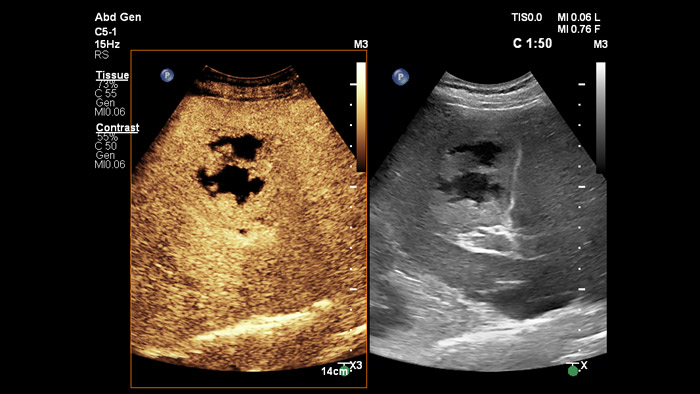

Os agentes de contraste de ultrassons podem transformar o papel da ecografia, permitindo que os médicos estudem os padrões de melhoria de lesões hepáticas em tempo real. Com os ecógrafos da Philips, a ecografia com realce por contraste está perfeitamente integrada no fluxo de trabalho padrão.